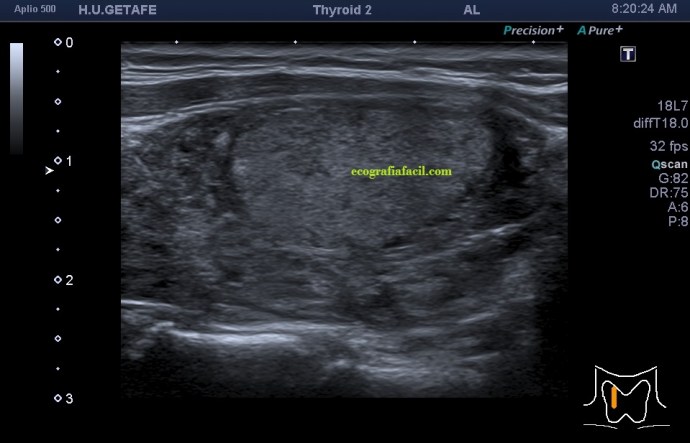

De la imagen 1 a 7 el protocolo habitual, el estudio particular del nódulo con medidas y aplicación del doppler demuestra el aspecto típico del Caballero Blanco.

La imagen 12 y 13 están adquiridas con una sonda de 18 Mhz.

- Hipoecogenicidad del parénquima

- Heteroecogenicidad

- Múltiples nódulos hipoecoicos muy pequeños